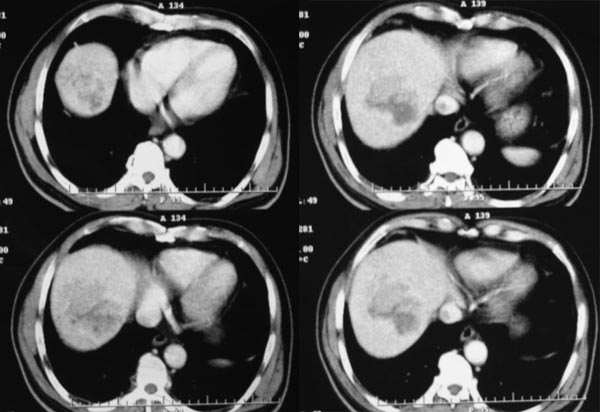

门脉期

延时期

从动脉期到延时期可见病灶内有星芒样不强化裂隙,考虑fnh。鉴别:1血管瘤,逐渐强化,延时期造影剂填充呈高密度。2肝癌,早进早出。

平扫:团块状低密度灶,动脉期:边缘环形强化,门脉期:增强逐步向中心推进,实质期:强化进一步明显,中心呈裂隙样无强化影。所以首先考虑血管瘤

早期强化不是很明显,血供不是很丰富,与肝实质相比还是呈快进快出的特点,中心裂隙样坏死,支持原发性肝癌。